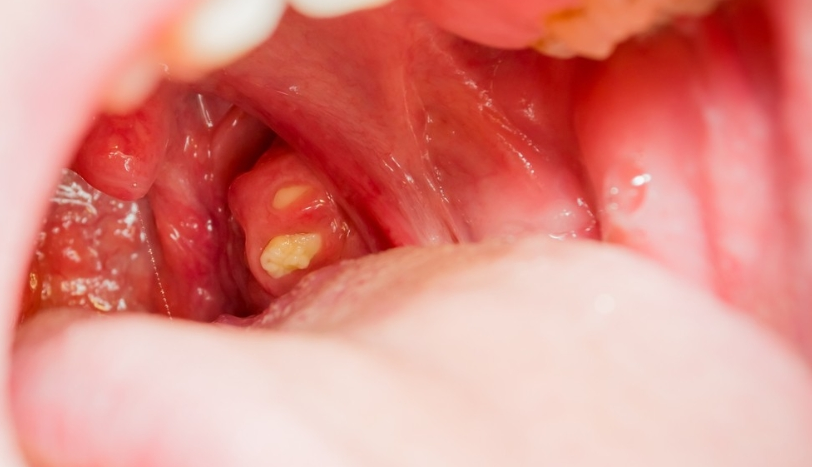

편도결석은 편도 표면에 존재하는 작은 구멍(편도음와) 사이에 음식 찌꺼기나 세균이 결합된 쌀알 같은 알갱이가 생성된 것을 의미합니다.

5밀리미터 정도의 쌀알 크기에서 1.5센티미터 정도의 거대한 결석이 관찰되기도 합니다. 기침이나 가래를 뱉는 등의 행동에 의해 자연스럽게 배출될 수도 있지만, 처치 없이는 제거되지 않는 유형도 있습니다.

• 침이나 음식 등을 삼킬 때 뭔가가 걸리는 듯한 이물감이 느껴집니다.• 목 안이 근질근질한 느낌이 들어요.• 입안을 플래시로 비추거나 관찰하면 노란색 알갱이가 보입니다.• 구강 청결을 유의함에도 불구하고 물고기의 비린내와 비슷한 구취가 발생합니다.• 메스꺼움이나 기침, 가래를 뱉는 등의 행동을 할 때 입자가 튀어나옵니다.• 별다른 병증이 없어도 기침이 나요.• 음식을 섭취하지 않아도 무언가가 목 뒤에 쓰러져 있는 것 같은 생각이 듭니다.